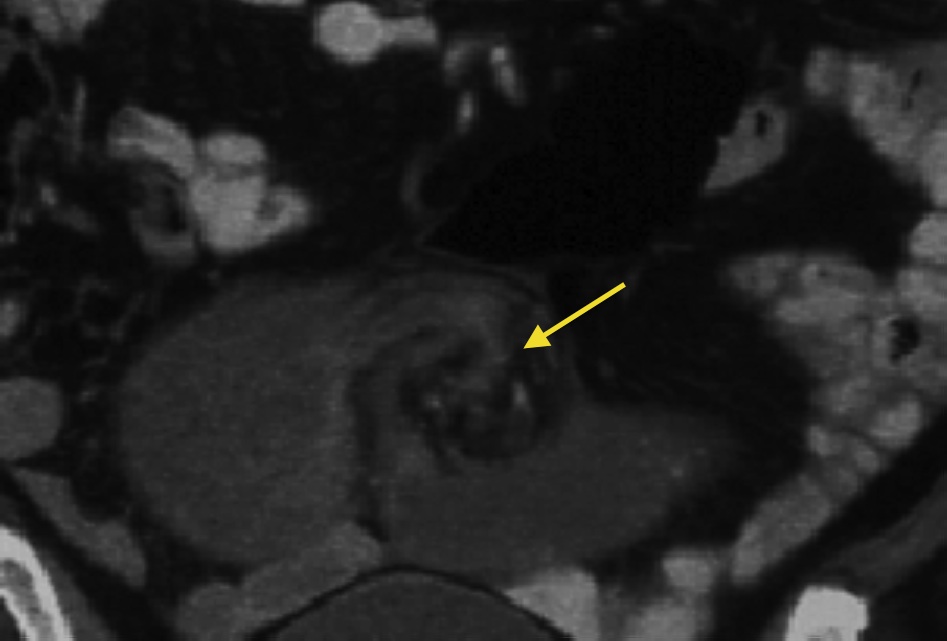

Small bowel obstruction is a common clinical presentation that presents a diagnostic conundrum. Over the last 2 decades, there has been a paradigm shift in the radiological investigation of small bowel obstruction (SBO) and in the indication for and timing of surgical intervention. Cross sectional imaging (predominantly computed tomography) has largely replaced the widespread use of radiographic small bowel follow-through studies as the imaging modality of choice for SBO. This article illustrates the current imaging modalities available for diagnosis of small bowel obstruction. (Full text available online at www.medpharm.tandfonline.com/ojfp) S Afr Fam Pract 2015; DOI: /10.1080/20786190.2014.977052